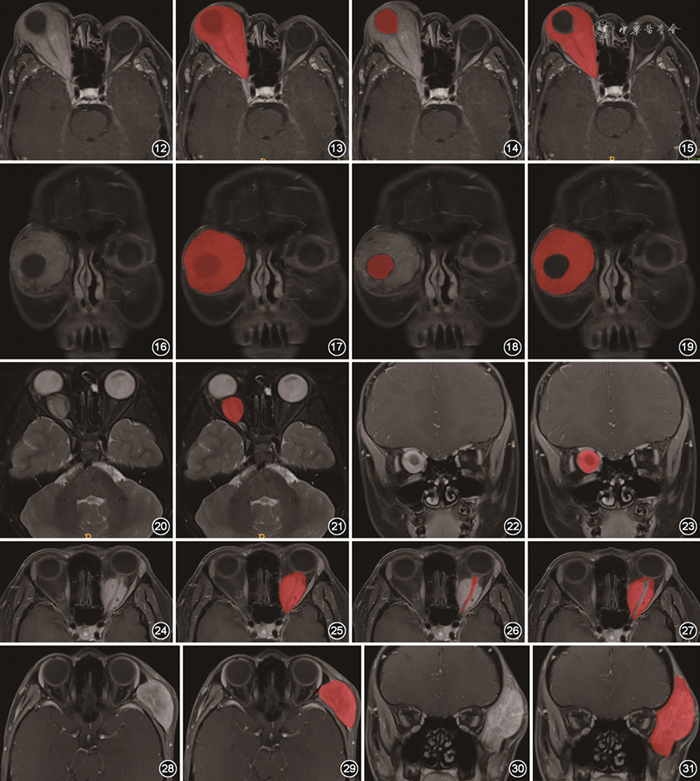

(3)包绕眼球的肿块。当肿块包绕眼球不超过1/2眼周时,采用直接勾画的方式完成标注;当肿块生长超过1/2眼周时,勾画时要特别注意“首尾重叠”,避免遗漏病变;当肿块完全包绕眼球时,结合横断面T2WI及增强T1WI图像进行标注,首先标注肿块整体和眼球,然后单独标注眼球,前者减去后者即为肿块,勾画示意图见图12~19。

图12~19 眼眶肿块完全包绕眼球的勾画示意图。病理证实为淋巴瘤,肿块完全包绕眼球。首先标注肿块整体和眼球(图12,13),再单独标注眼球(图14),两者减影后获得标注肿块的图像(图15)。图16~19为相应冠状面图像

(4)视神经及视神经鞘肿块。①视神经肿块,联合T2WI和增强T1WI图像,沿病变显示最大轮廓标注,勾画示意图见图20~23。②视神经鞘肿块,在横断面脂肪抑制增强T1WI图像标注,首先标注肿块整体和视神经,然后标注未强化的视神经,前者减去后者即为视神经鞘肿块,勾画示意图见图24~27。③视神经及视神经鞘肿块累及颅内时,同时标注颅内病变。

(5)眶壁及眶骨膜下肿块。结合平扫T1WI和脂肪抑制增强T1WI,对整个肿块进行标注,勾画示意图见图28~31。